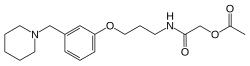

Принята следующая классификация H2-блокаторов по поколениям[4]:

- I поколение — циметидин,

- II поколение — ранитидин,

- III поколение — фамотидин,

- IV поколение — низатидин,

- V поколение — роксатидин.

Циметидин, H2-блокатор I поколения, обладает серьёзными побочными проявленими: он блокирует периферические рецепторы мужских половых гормонов (андрогенные рецепторы), существенно снижая потенцию и приводит к развитию импотенции и гинекомастии. Также возможны диарея, головные боли, транзиторные артралгии и миалгии, блокирование системы цитохрома Р450, повышение уровня креатинина в крови, поражение центральной нервной системы, гематологические изменения, кардиотоксические эффекты, иммуносупрессивное действие[1][2].

Ранитидин имеет меньше типичных для циметидина побочных эффектов, а препараты последующих поколений — ещё меньше. При этом активность фамотидина в 20—60 раз превышает активность циметидина и в 3-20 раз активность ранитидина. По сравнению с ранитидином фамотидин более эффективно повышает pH и снижает объем желудочного содержимого. Длительность антисекреторного действия ранитидина — 8-10 часов, а фамотидина — 12 часов[1].

H2-блокаторы IV и V поколений низатидин и роксатидин на практике мало чем отличаются от фамотидина и не имеют перед ним существенных преимуществ, а роксатидин даже немного проигрывает фамотидину в кислотоподавляющей активности[4].